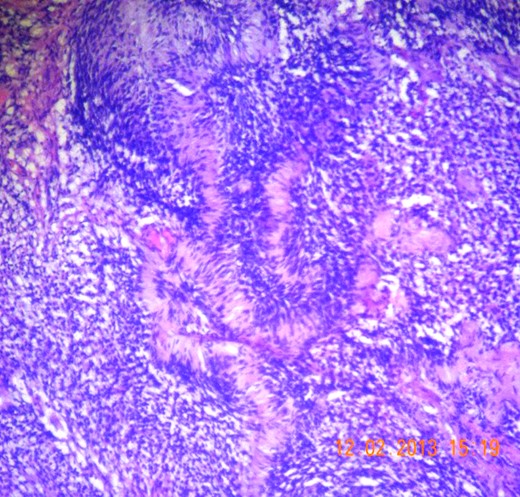

Gross appearance showed 6 × 4 × 4 cm smooth encapsulated right thyroid swelling with a posterior cystic area which was yellowish brown in colour. Walls of the cyst were bright yellow with polypoid areas (Fig. 4). Histology showed classical Antoni A (hypercellular areas) with Verocay bodies and Antoni B (hypocellular) pattern, with interspersed thyroid cells along the periphery (Figs 5–7). The lesion was reported to be arising from within the thyroid gland itself and not extrinsic to it.

Microscopic section (H&E slide, 40×) of well-encapsulated lesion with hyper- (Antoni A) and hypocellular (Antoni B) areas. Multiple cystic areas are also seen.

Microscopic section (H&E slide, 40×) of Verocay bodies within Antoni A pattern.

Microscopic section (H&E slide, 100×) of magnified view of a region in Fig. 6 showing Verocay bodies.